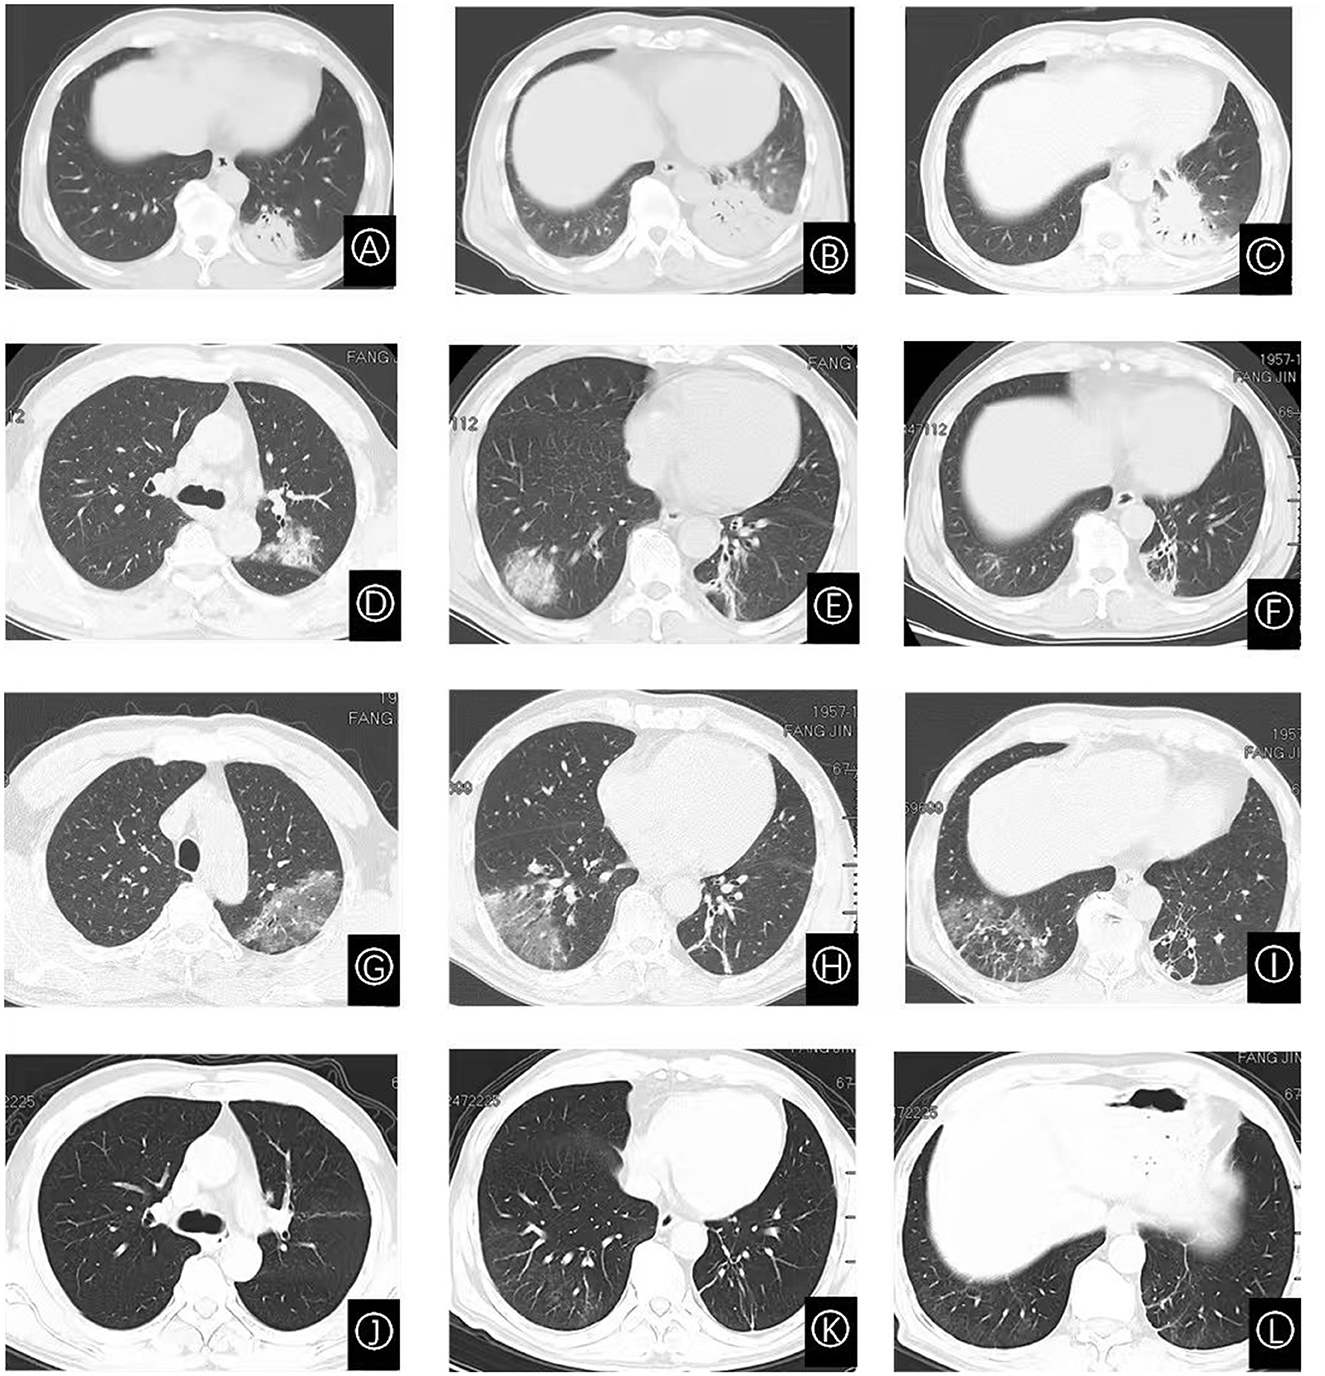

Nine days prior to admission, he developed a fever of unknown origin, accompanied by chills, rigors, headache, and dizziness during febrile episodes. On the fifth day of illness, a chest CT scan showed patchy dense opacities in the left lower lobe basal segment, featuring mixed ground-glass and consolidation shadows (Figure 1A). Treatment with intravenous ceftizoxime (2 g every 12 h) was initiated. However, his fever persisted and was followed by the onset of cough, sputum production, and blood-streaked sputum. A repeat chest CT revealed progression of consolidation in the same lung region (Figure 1B), prompting hospital admission.

Figure 1

Serial chest CT images demonstrating the dynamic evolution of pulmonary lesions. (A) CT scan obtained on day 5 of illness shows an exudative shadow in the left lower lobe. (B) Scan on day 8 reveals interval enlargement of the lesion in the left lower lobe. (C) By day 14, the exudative shadow shows signs of absorption compared to (B). (D–F) CT images on day 26 demonstrate new, multifocal bilateral pulmonary involvement, featuring exudative shadows, ground-glass opacities, consolidations, and migratory lesions. (G–I) Follow-up on day 37 shows persistent pulmonary lesions with no significant improvement. (J–L) Scan on day 48, following glucocorticoid therapy, shows near-complete resolution of the pulmonary abnormalities.

During outpatient follow-up 9 days after discharge (illness day 26), repeat chest CT demonstrated partial resolution of left lower lobe inflammation but revealed new infiltrates in the left upper and right lower lobes (Figures 1D–F). Thirteen days post-discharge, the patient experienced recurrent fever (peak 39 °C) accompanied by rhinorrhea, though without cough or sputum. He was readmitted for further evaluation; laboratory results are shown in Table 1.

After 11 days of minocycline (100 mg orally every 12 h), repeat CT showed no significant radiographic improvement (Figures 1G–I). Given the clinical picture of recurrent fever with migratory pulmonary lesions, the prior biopsy specimen was re-examined and pathologically diagnosed as OP (Figure 2). Methylprednisolone 40 mg daily was initiated. Doxycycline was continued throughout this period due to the concomitant C. psittaci infection. After 10 days of combined therapy (illness day 48), chest CT showed near-complete resolution of bilateral pulmonary infiltrates (Figures 1J–L). Corticosteroid tapering was initiated 2 weeks later at a rate of 5 mg per week until discontinuation.